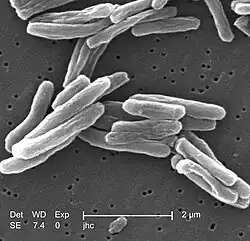

Původce

Hlavním původcem tuberkulózy, Mycobacterium tuberculosis (MTB), je malá aerobní tyčinkovitá bakterie. Vysoký obsah lipidů způsobuje mnoho z jejích výjimečných vlastností.[49] Dělí se každých 16–20 hodin, což je v porovnání s ostatními bakteriemi, které se většinou dělí za méně než hodinu, extrémně pomalé.[50] Protože MTB má buněčnou stěnu, ale ne dvojici vnější a vnitřní plazmatické membrány, je klasifikována jako grampozitivní bakterie. Během Gramova barvení se ale kvůli vysokému obsahu lipidů v buněčné stěně barví buď velmi málo nebo vůbec.[51] MTB je schopna odolat slabé dezinfekci a dokáže přežít několik týdnů v suchém stavu. V přírodě může růst pouze v buňkách hostitele, ale lze ji pěstovat in vitro.[52]

Pomocí barvících mikrobiologických metod lze M. tuberculosis detekovat ve sputu. Nejčastěji používanou metodou je Ziehl-Neelsenovo barvení, při kterém se M. tuberculosis zbarví červeně. K vizualizaci MTB lze využít i směs auramin-rhodamin a fluorescenční mikroskopii.

Do komplexu M. tuberculosis, což je skupina geneticky blízkých mykobakterií, které způsobují tuberkulózu, patří ještě M. bovis, M. africanum, M. canetti a M. microti.[53] M. africanum není hojně rozšířená, ale v některých částech Afriky patří mezi důležité původce tuberkulózy.[54][55] M. bovis byla v minulosti běžnou příčinou tuberkulózy lidí, ale zavedením metody pasterizace mléka se infekce tímto druhem téměř eliminovala.[3][56] M. canetti je výjimečná a vyskytuje se téměř výhradně v Africe, i když bylo zaznamenáno několik případů výskytu této bakterie u afrických emigrantů.[57] M. microti je nejčastěji pozorována u lidí s poškozenou imunitou, i když je možné, že prevalence tohoto patogenu byla podceněna.[58]